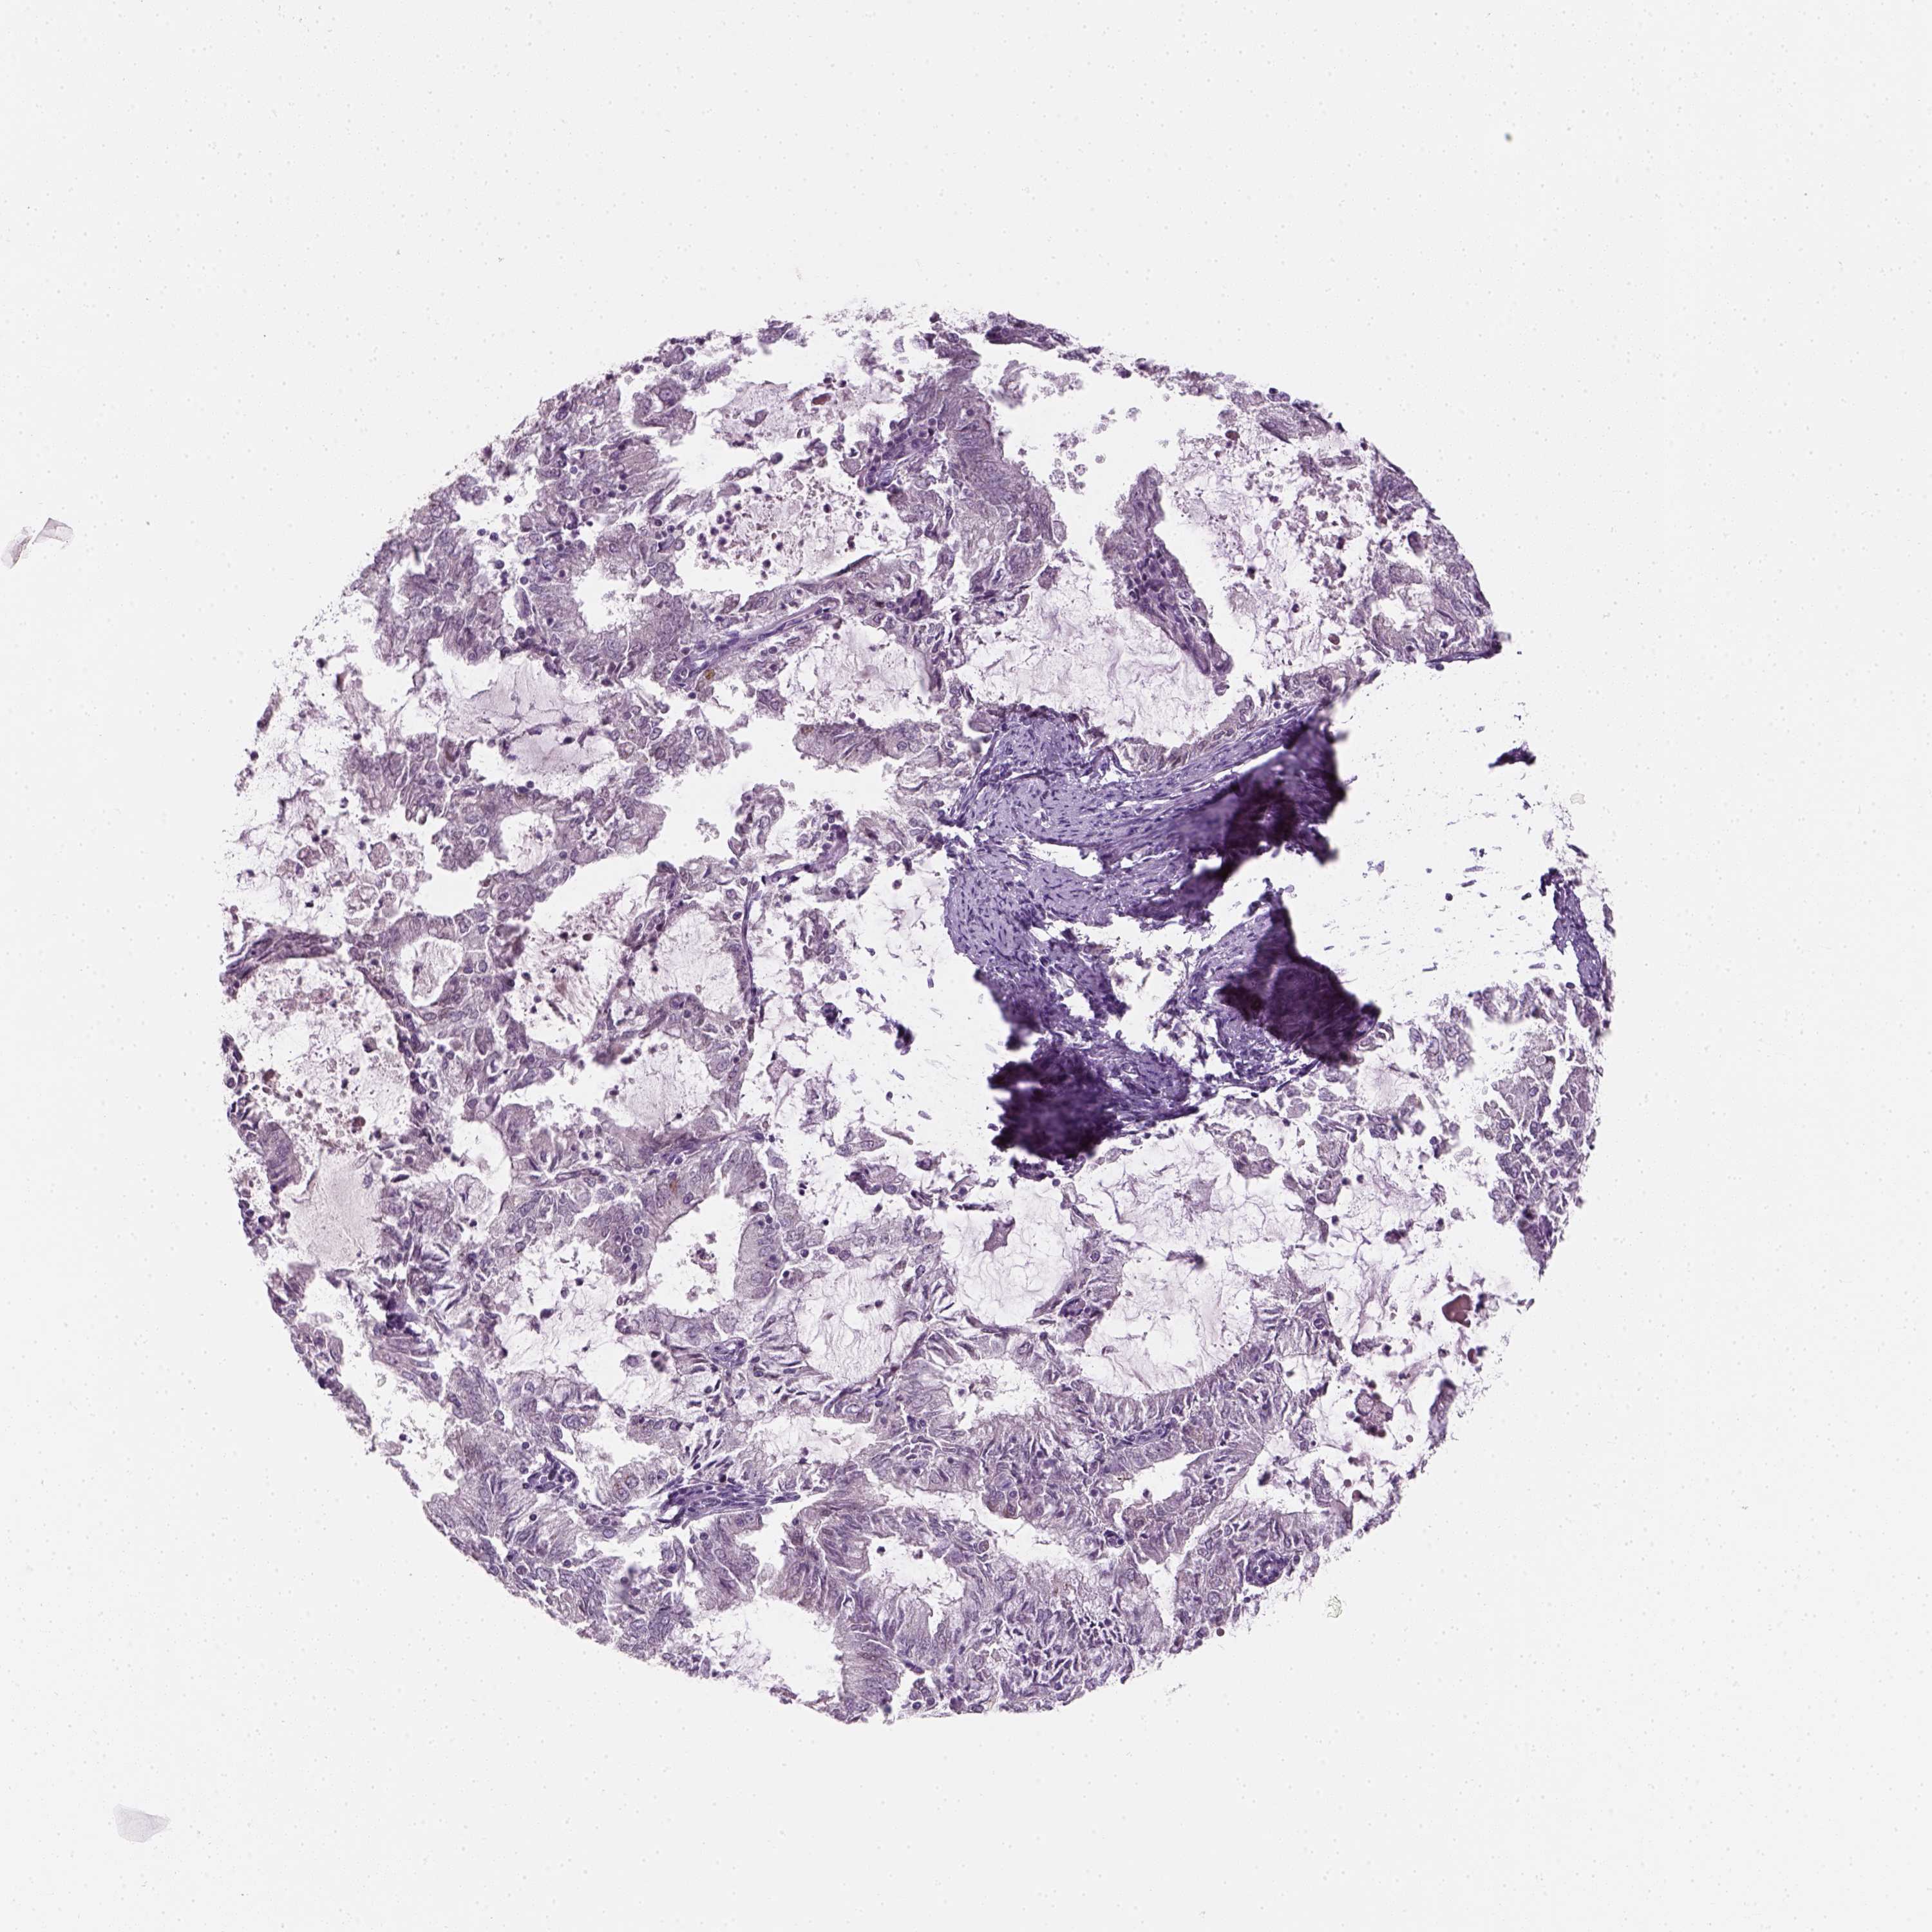

ENDOMETRIAL CANCER - Protein expressioni

A mouse-over function shows sample information and annotation data. Click on an image to view it in a full screen mode. Samples can be filtered based on level of antibody staining by selecting one or several of the following categories: high, medium, low and not detected. The assay and annotation is described here.

Note that samples used for immunohistochemistry by the Human Protein Atlas do not correspond to samples in the TCGA dataset.

Antibody stainingi

Antibody staining in the annotated cell types in the current human tissue is reported as not detected, low, medium, or high, based on conventional immunohistochemistry profiling in selected tissues. This score is based on the combination of the staining intensity and fraction of stained cells.

Each image is clickable and will lead to virtual microscopy that enables deeper exploration of all samples and also displays staining intensity scores, fraction scores and subcellular localization as well as patient and tissue information for each sample.

Antibody CAB002973

Antibody CAB039238

Antibody CAB039239

Antibody CAB072876

Staining

High

Medium

Low

Not detected

Intensity

Strong

Moderate

Weak

Negative

Quantity

>75%

75%-25%

<25%

None

Location

Nuclear

Cytoplasmic/membranous

Cytoplasmic/membranous,nuclear

Adenocarcinoma, NOS

Neoplasm, malignant, NOS

Adenocarcinoma, metastatic, NOS